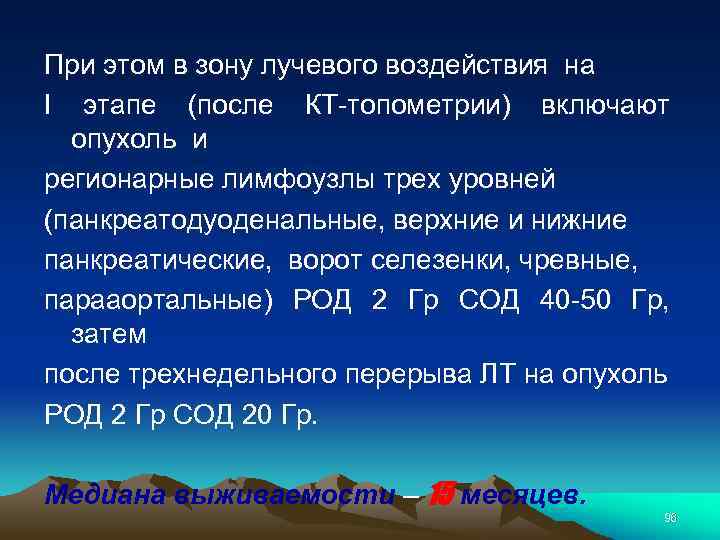

При этом в зону лучевого воздействия на I этапе (после КТ-топометрии) включают опухоль и регионарные лимфоузлы трех уровней (панкреатодуоденальные, верхние и нижние панкреатические, ворот селезенки, чревные, парааортальные) РОД 2 Гр СОД 40 -50 Гр, затем после трехнедельного перерыва ЛТ на опухоль РОД 2 Гр СОД 20 Гр. Медиана выживаемости – 15 месяцев. 96